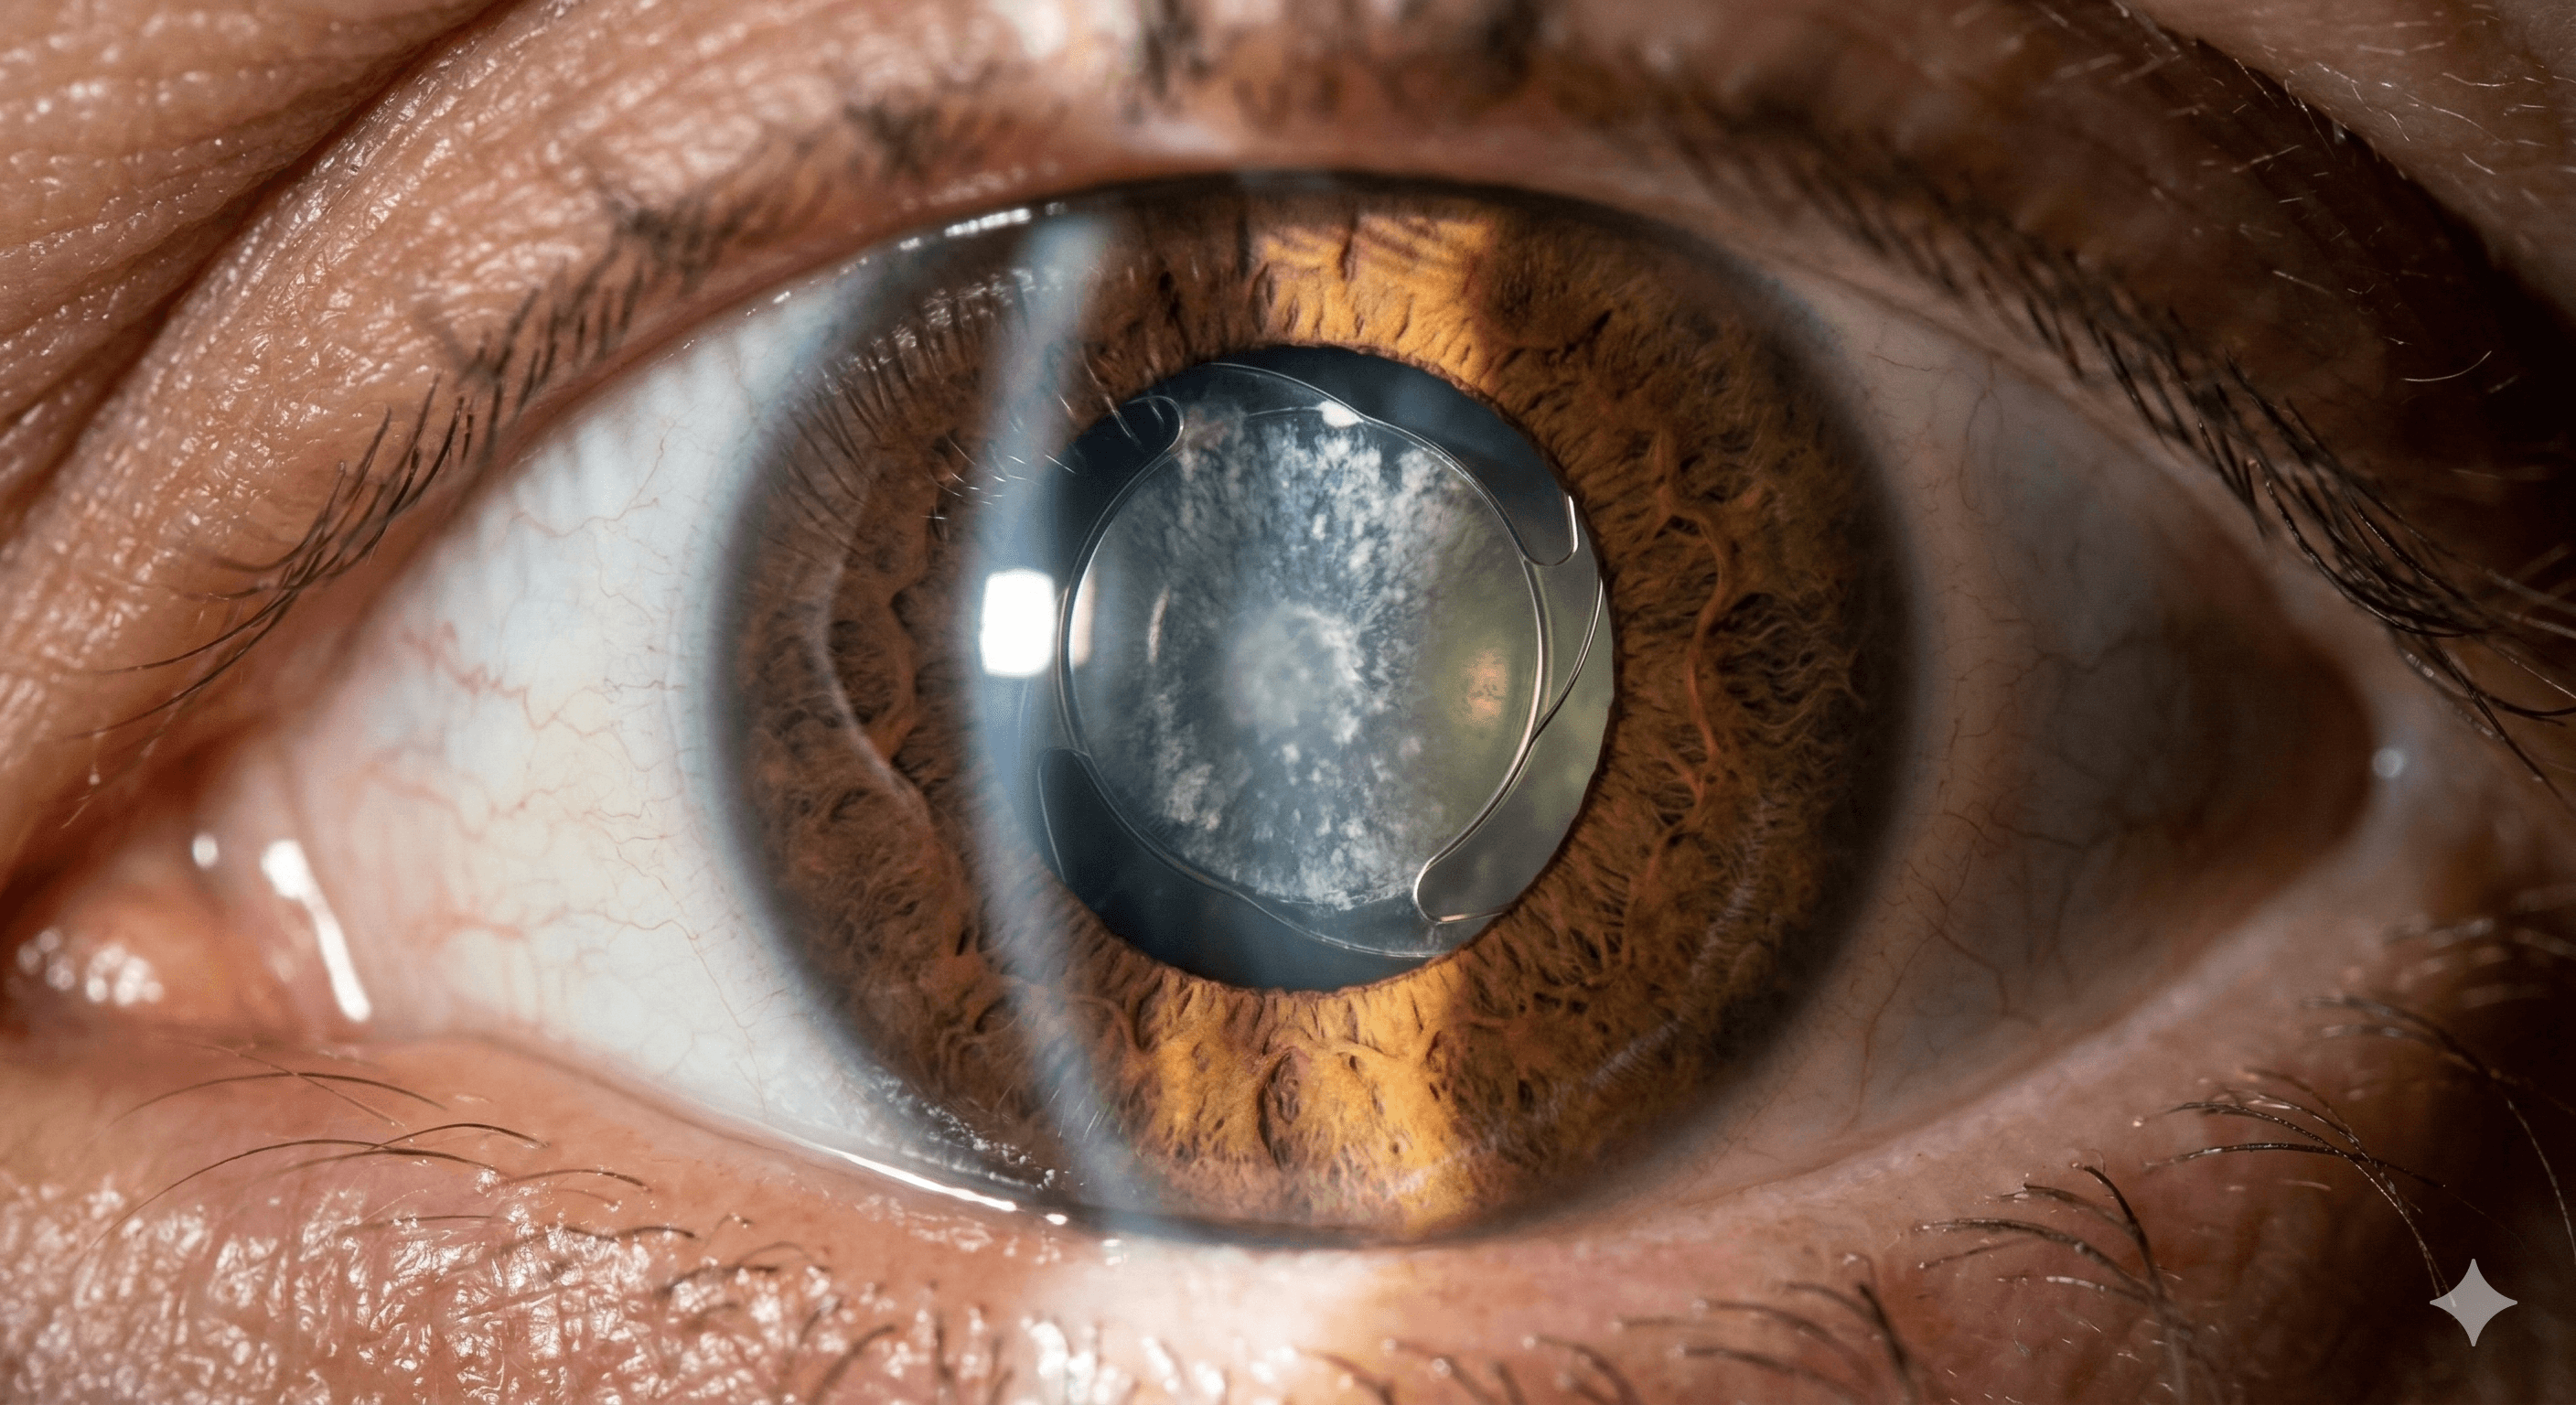

Catarata (senil, congénita y traumática)

La catarata es la pérdida de transparencia del cristalino, el lente natural del ojo. Puede ser causada por la edad, golpes o nacer con ella....

Complicaciones posteriores a cirugía de catarata

Atención especializada para situaciones inesperadas o efectos secundarios tras una intervención de cristalino....

Opacidad de cápsula posterior

Comúnmente llamada 'limpieza de lente', es una nubosidad que se forma detrás del lente intraocular meses o años después de la cirugía....